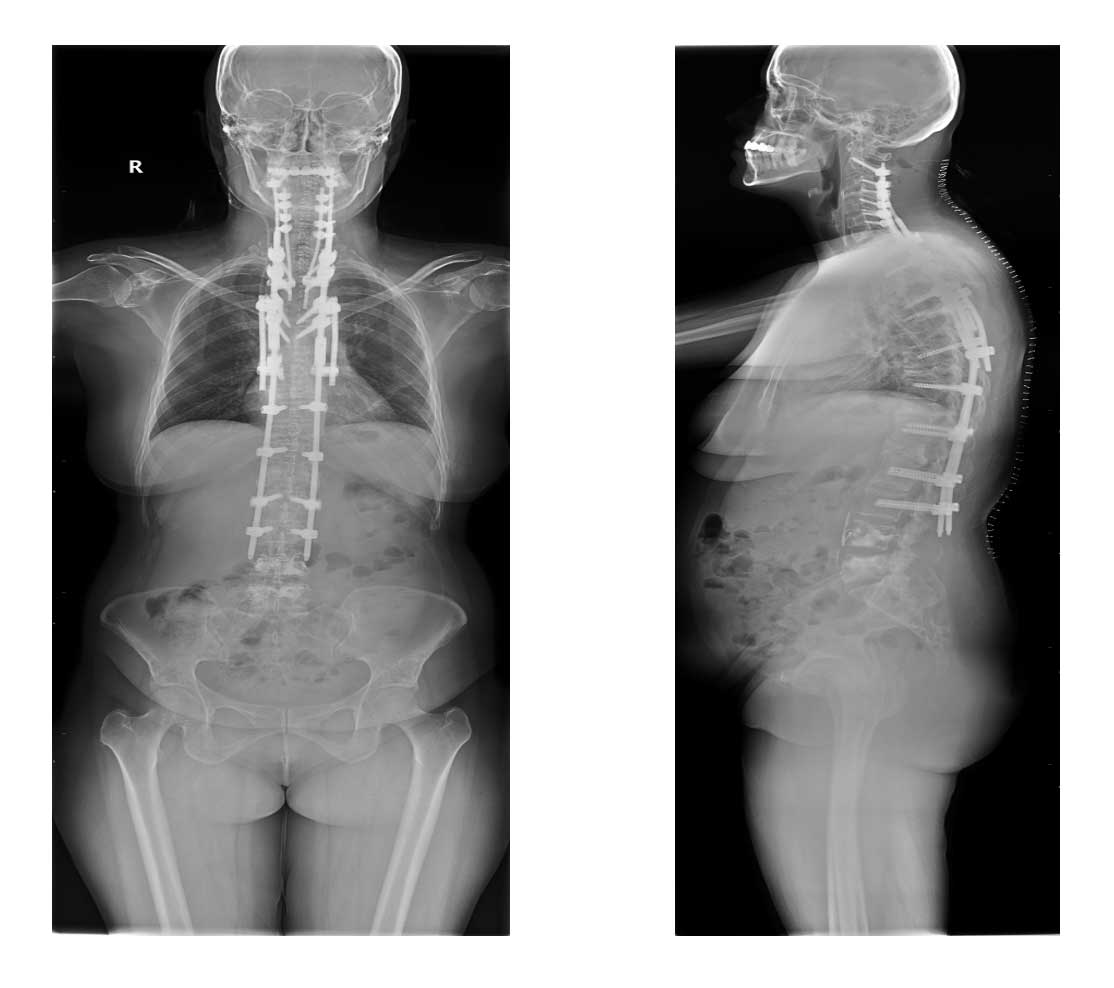

Ameliyat Esnası: Boyun ve sırt bölgesinde açık bel bölgesinde kapalı vidalama işlemi görülmekte.

Ameliyat sonrası: Röntgende vidalama (C2-L3 posterior enstrümentasyon) ve çimentolama (L4-5 vertebroplasti) işlemi görülmekte.